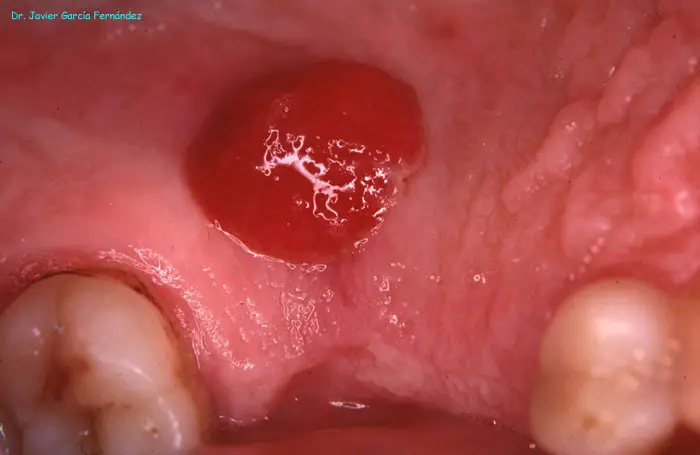

Atlas of Surgical Techniques in Periodontics. Chapter I. Diagnostic of Peridontal Diseases. Classification. Atlas de Técnicas Quirúrgicas en Periodoncia. Cap. I. Classification. Atlas de Técnicas Quirúrgicas en Periodoncia